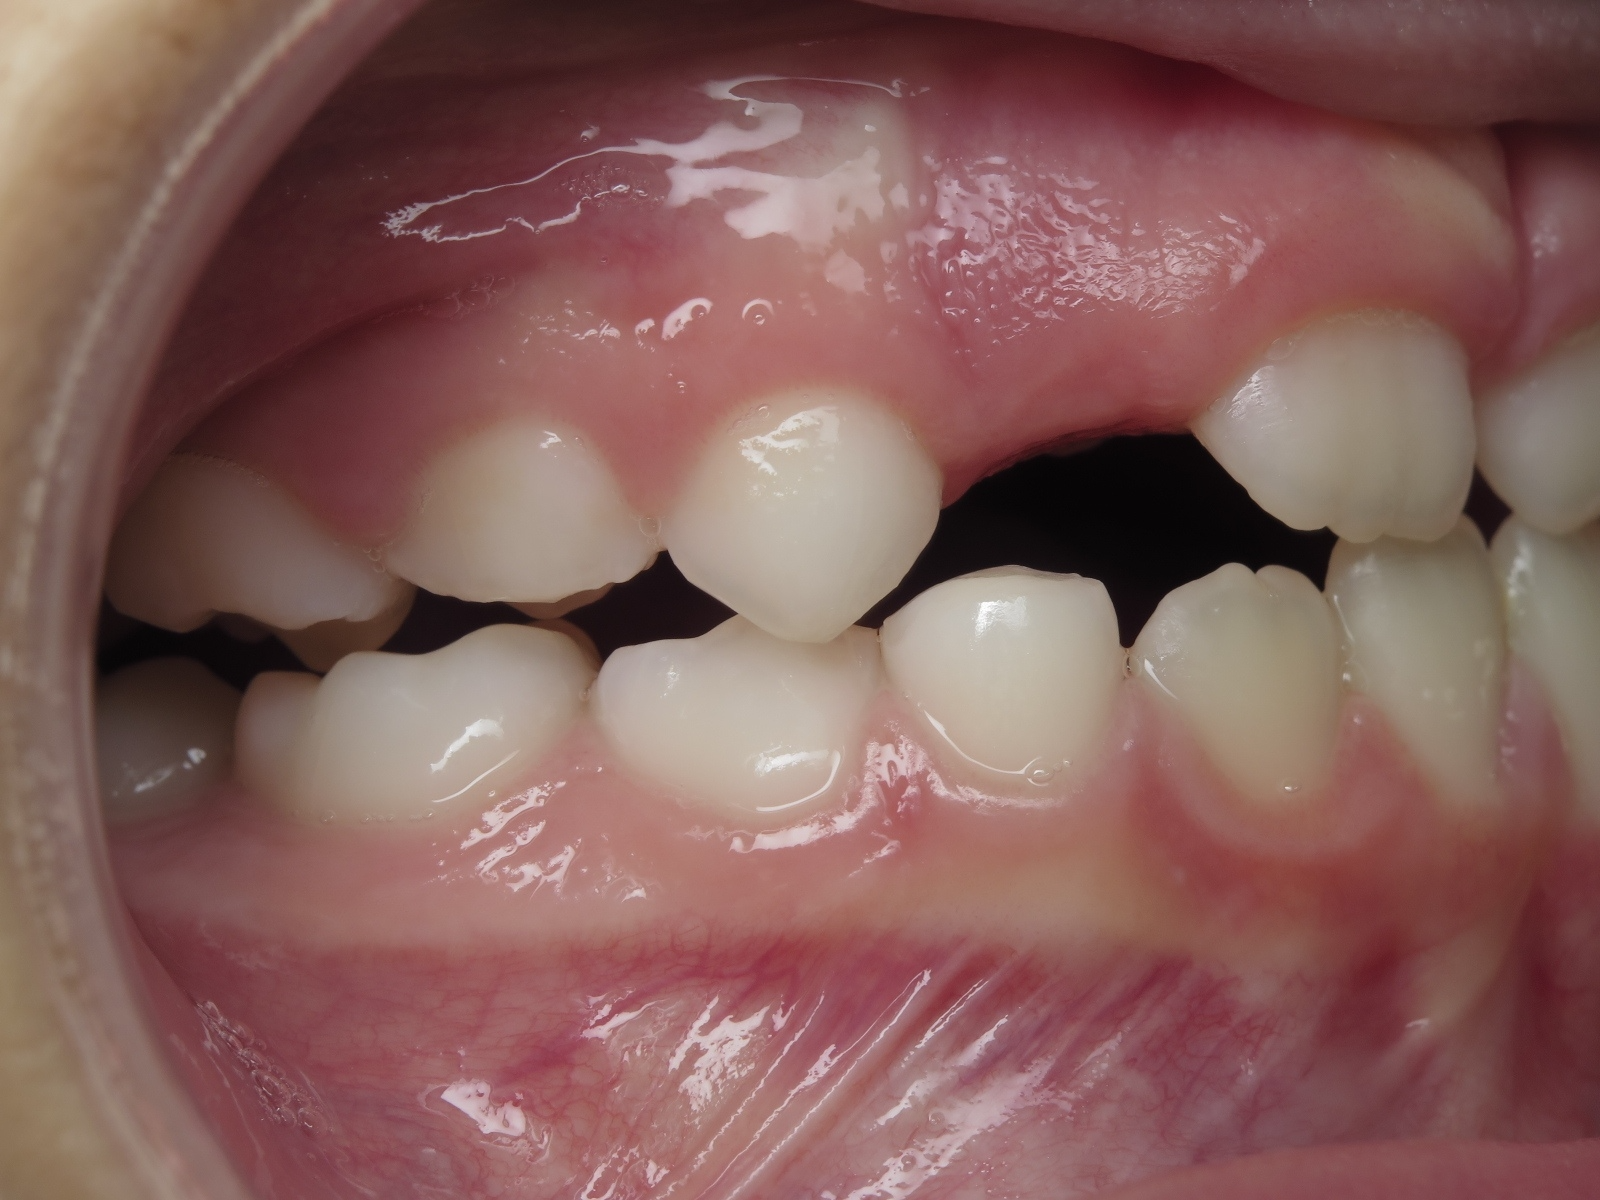

25. bout à bout anterieur 6 ans

dents du haut bout à bout par rapport à celle du bas